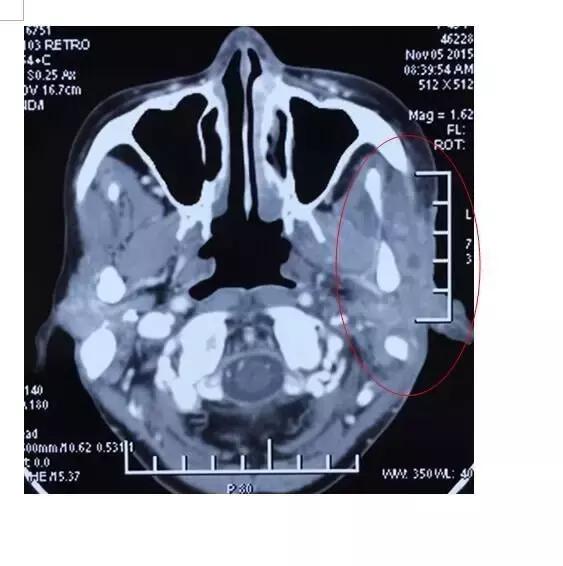

A45治疗一个疗程后

吴女士的发病毫无征兆,两年前一次无意中在脸上摸到肿物,到医院检查后,被确诊为腺泡细胞癌,随即前往国内权威肿瘤医院进行手术切除患侧腮腺,并行瘤床及高危淋巴结引流区放疗30次。本以为可以逃过一劫,不料,术后半年腮腺癌就复发了,肿瘤比原来的还要大,二次手术后不到两个月,右耳前皮下再次出现肿物,并逐渐增大,右耳前皮肤开始出现水泡,后逐渐增多,多次复发的她已对治疗失去了信心,甚至想放弃治疗。家人的支持让她重拾信心,慕名找到全球肿瘤医生网,在前往苏州大学附属肿瘤医院接受治疗前的检查,发现肺部也出现转移灶,她抱着试试看的心情接受了A45肿瘤动力治疗,经过全身和局部的A45肿瘤动力治疗后,病灶缩小非常明显,皮肤逐渐愈合好转。

A45治疗后